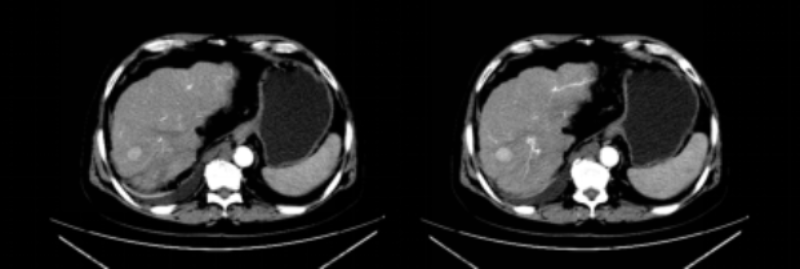

經(jīng)過1個多小時的手術(shù),腫瘤消融完全,周邊組織損傷很小,手術(shù)過程十分順利,楊大爺表示沒有任何不適,耐受性良好。1個月后返院復診,CT提示肝腫瘤完全滅活。

1個月后復查CT提示肝腫瘤完全消融